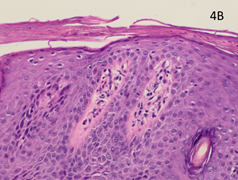

Figure 4A Pre-RT x 100 showing psoriasiform hyperplasia, loss of the granular layer and inflammation.

The pre-RT baseline biopsy was compared with the biopsies taken at eight weeks. The classic histological features of psoriasis are shown in the pre-RT biopsy (Figure 4A-C). There is psoriasiform hyperplasia and inflammation. The epidermis is thickened (a finding known as acanthosis), there is a loss of the normal granular layer, there is a thickened stratum corneum (a finding known as hyperkeratosis), and retention of nuclei in the upper layers and stratum corneum (a finding known as parakeratosis). There is suprapapillary thinning. There are abundant neutrophils in the epidermis and stratum corneum. In the dermis, there are abundant mononuclear cells, predominantly myeloid cells and T cells. There are several dilated dermal blood vessels which give the psoriasis plaques their characteristic erythema.3